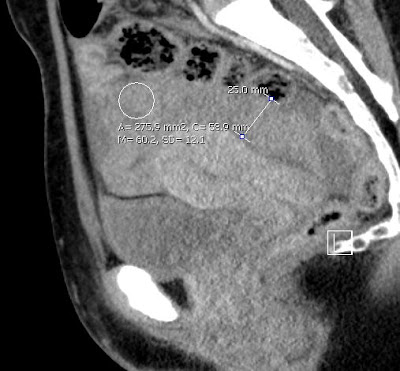

előzmény: 3 hete otthonában 6 hetes spontán vetélése zajlott. Beavatkozást nem igényelt. Tegnap délután intermittáló jellegű éles alhasi fájdalma kezdődött, hányinger kíséretében.

műtéti leírás: A hasüregben részben alvadékos vér található. A kismedencében az uterus egyenletesen megnagyobbodott, anteflexioban helyezkedik el. A vért szívóval részben eltávolítjuk ekkor észleljük, hogy a bal oldali kürtben középen kb 2 cm átmérőjű extauterin graviditás látható.